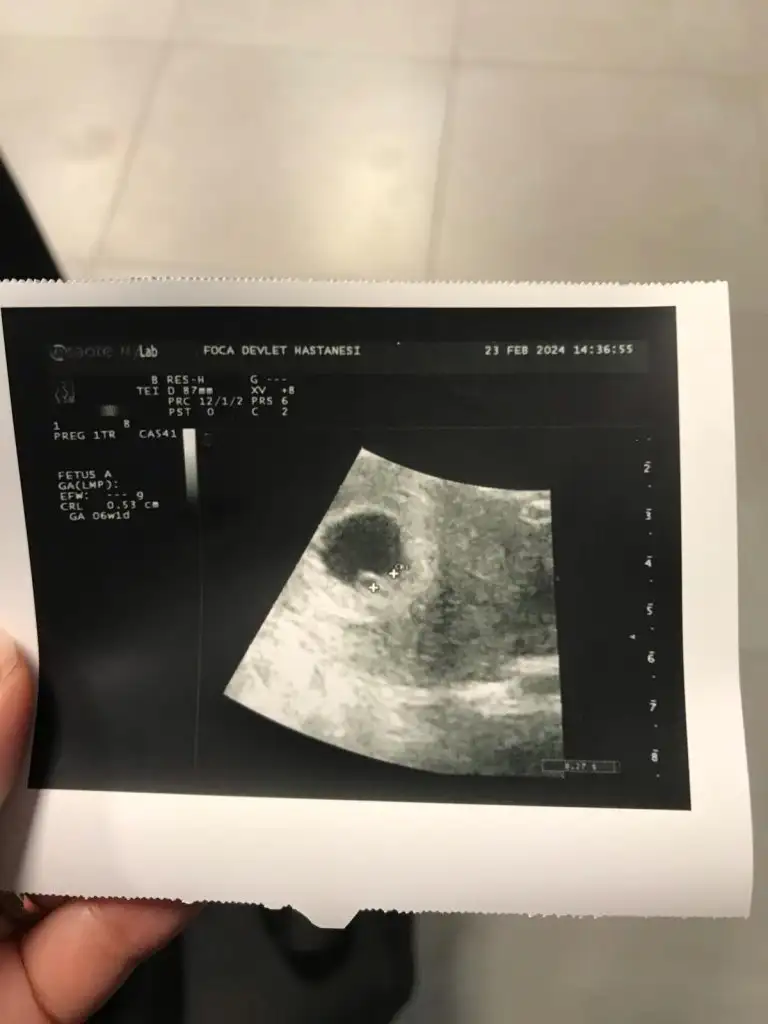

ben de araya kaynasam? daha önce buraya atmıştım ama hiç tahminde bulunan olmadı.ilki 6 hafta ikincisi 7+3.6-7 haftalık ultrason varmı yollar mısın Bi daha bakim merak ettim

doktor bir şey demedi ama.Vajinal ultrason ise erkek karın ultrasonu ise kızben de araya kaynasam? daha önce buraya atmıştım ama hiç tahminde bulunan olmadı.ilki 6 hafta ikincisi 7+3.

cuma günü ikili tarama için gittiğimde görüğüm şey kordon değilse erkek gibiydidoktor bir şey demedi ama.